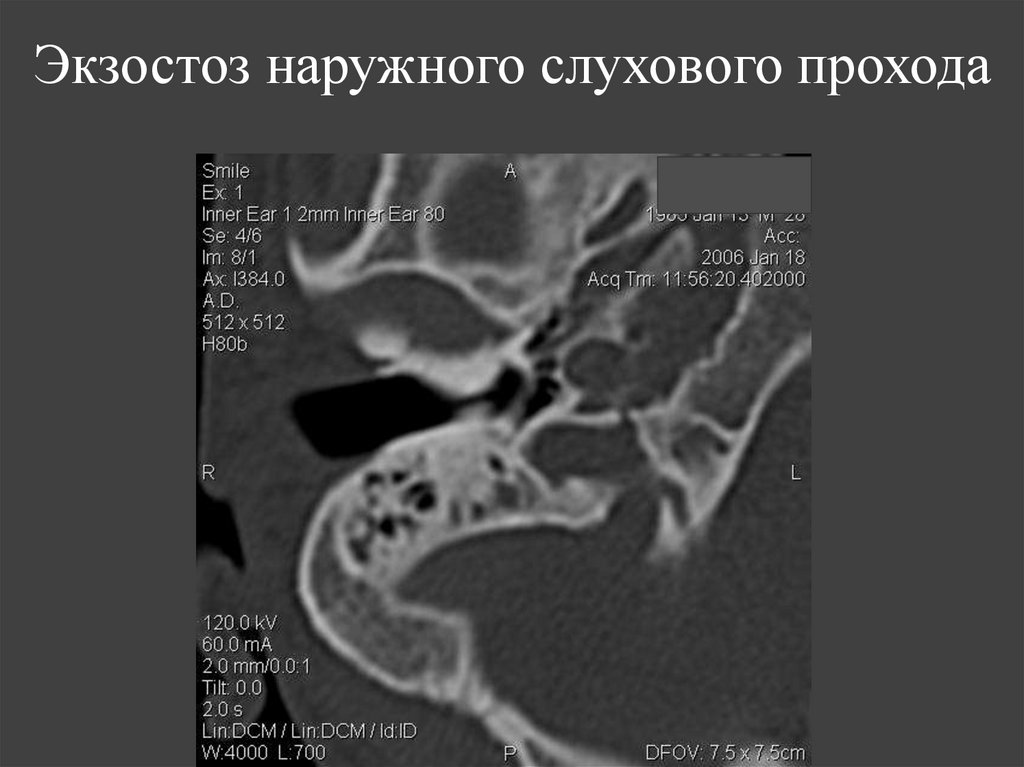

150. Экзостоз наружного слухового прохода

151.